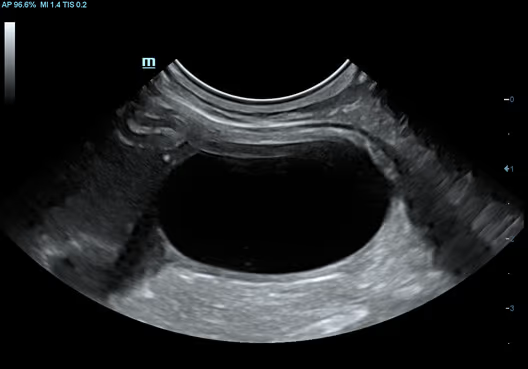

İdrar Kesesi, Kedi

İdrar Kesesi, Kedi